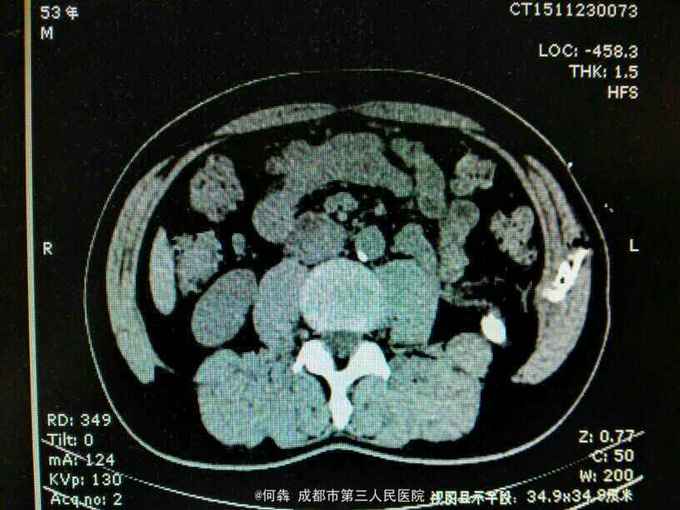

53岁,男性,因“腹腔镜下双肾囊肿切除术后1年余,左腰部窦道形成10月余”入院。无高血压病及糖尿病。

左腰部窦道形成伴少许脓液。窦道脓液培养出绿脓杆菌。

腹腔镜双肾囊肿切除术后窦道形成伴感染。现使用敏感抗生素派拉西林舒巴坦抗感染。